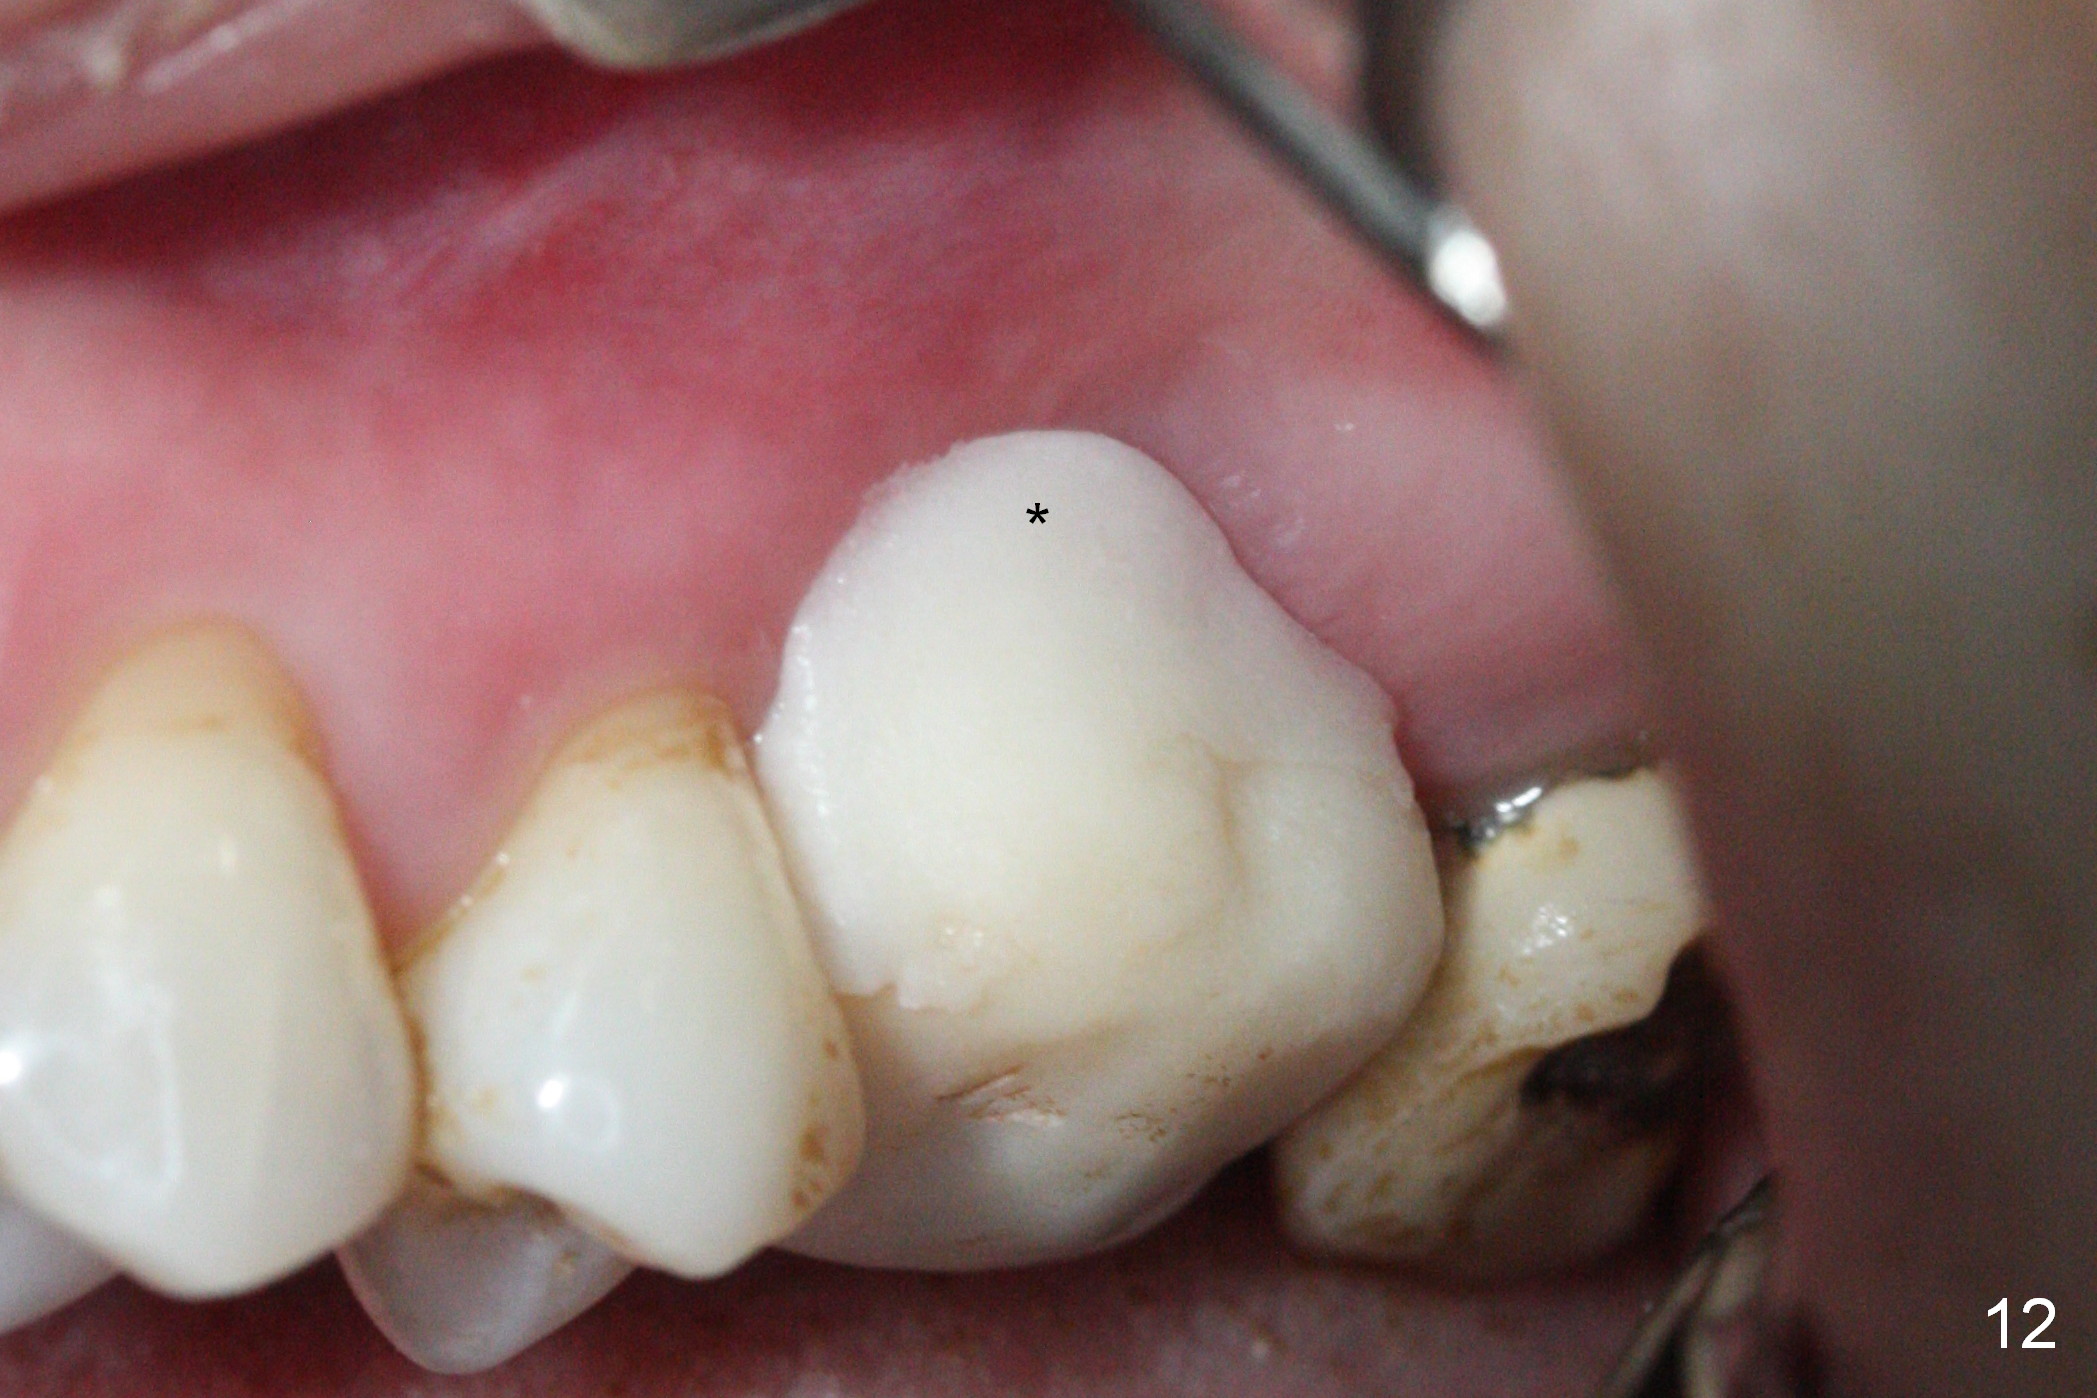

There is abundant subgingival calculus on the surfaces of the extracted tooth at #14 (Fig.1: P: palatal; MB: mesiobuccal), corresponding to the large empty socket (Fig.2 without septal bone, the buccal plate being low). Osteotomy is established palatally with Magic Expander (ME) 3.0 mm for ~ 3 mm deep (Fig.3,4) with minimal stability so that it moves during X-ray taking (Fig.4). Since the bone is dense, Magic drill 4.3 mm is used after application of ME 3.8 and 4.3 mm to complete sinus lift (Fig.5 (panoramic X-ray)). A 5x11 mm implant is placed with ~ 30 Ncm, followed by insertion of 6.5x4(3) mm Hexa abutment, bone graft and collagen membrane (Fig.6). The latter is kept in placed with an immediate provisional with clearance from the opposing dentition (Fig.7 *). Between the 1st and 3rd weeks postop, the buccal gingiva recedes with loss of bone graft (Fig.8 <) and implant thread exposure (Fig.9 * (A: abutment)). After inducing hemorrhage, allograft is placed (Fig.10 >), followed by collagen dressing (Fig.11 >). The wound closes by adding new acrylic (Fig.12 *). Thirteen days later, food is trapped in the buccal gap (Fig.13 ^). It appears that the provisional does not help wound healing. The provisional and abutment are removed; incorporating bone graft (Fig.14 *) and the implant are exposed. After placing collagen plug against the bone graft and implant, the wound is closed by periodontal dressing.

The implant is stable 8 months postop (Fig.15). When a 6x4(3) mm abutment is placed 8.5 months postop, it is distal (Fig.16). The mesiodistal width is 1-2 mm shorter than that at #3, which suggests the mesial shift of the tooth #15. A provisional is fabricated at #14 (Fig.17 P) with supra-occlusion so that there is clearance between the tooth #15 and the opposing one (Fig.18 *). With a separator placed between #14 and 15 (Fig.19), the latter is free to be distalized. Bone volume and density seem to increase 4.5 and 10.5 months post cementation (Fig.20,21, as compared to Fig.15), although the buccal plate remains as concave as shown in Fig.18. One year 5 months post cementation, the patient complains of bad smell from the implant when water pik is being used. It appears that the 1st 2-3 threads are exposed (Fig.22), although the surrounding gingiva remains uninfected. Bone graft is recommended. The site heals without bad smell 7 months post bone graft (2 years 4 months post cementation, Fig.23). The 1st implant thread is found exposed buccal on uncover (regraft?). A small healing abutment is placed because the implant is placed distal (Fig.24). An angled abutment should be tried and #15 crown will be redone. Impression will be taken when the gingiva heals around the provisional crowns.